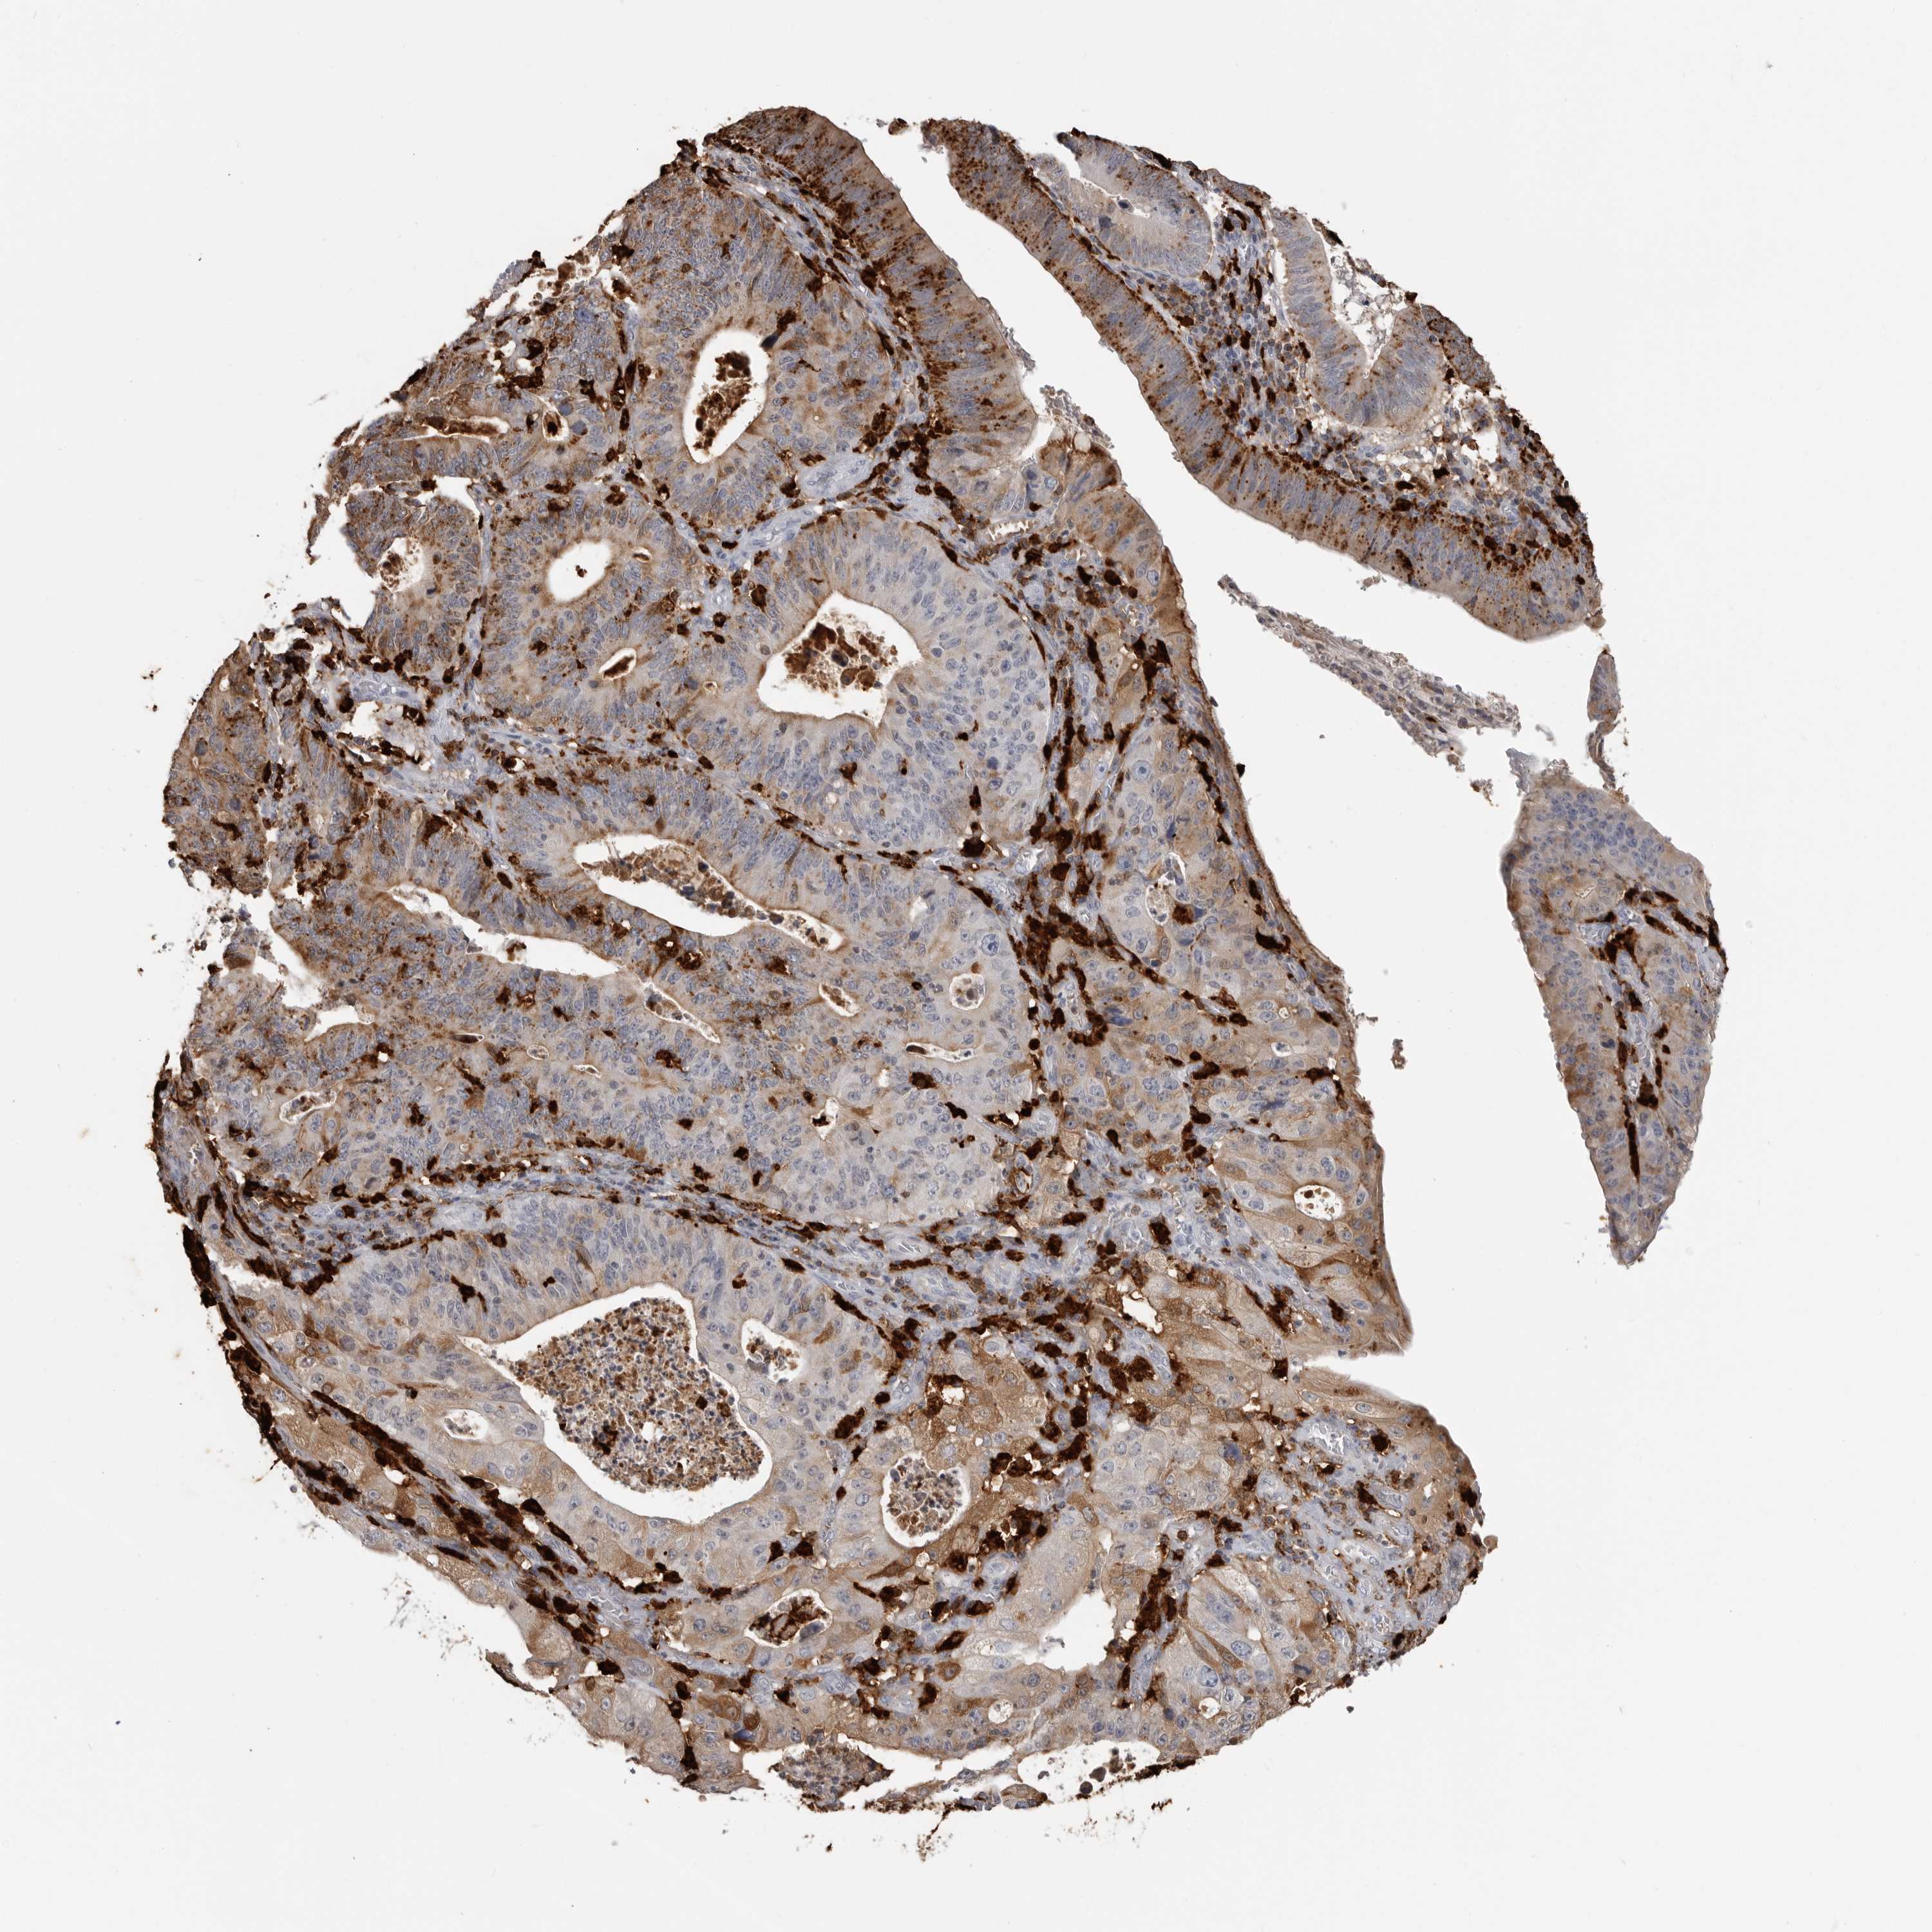

STOMACH CANCER - Protein expressioni

A mouse-over function shows sample information and annotation data. Click on an image to view it in a full screen mode. Samples can be filtered based on level of antibody staining by selecting one or several of the following categories: high, medium, low and not detected. The assay and annotation is described here.

Note that samples used for immunohistochemistry by the Human Protein Atlas do not correspond to samples in the TCGA dataset.

Antibody stainingi

Antibody staining in the annotated cell types in the current human tissue is reported as not detected, low, medium, or high, based on conventional immunohistochemistry profiling in selected tissues. This score is based on the combination of the staining intensity and fraction of stained cells.

Each image is clickable and will lead to virtual microscopy that enables deeper exploration of all samples and also displays staining intensity scores, fraction scores and subcellular localization as well as patient and tissue information for each sample.

Antibody HPA026650

Staining

High

Medium

Low

Not detected

Intensity

Strong

Moderate

Weak

Negative

Quantity

>75%

75%-25%

<25%

None

Location

Nuclear

Cytoplasmic/membranous

Cytoplasmic/membranous,nuclear

Adenocarcinoma, NOS